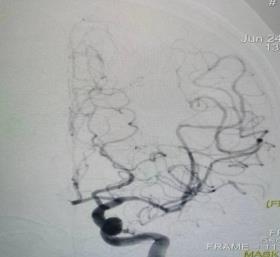

科室除常规开展脑梗死、脑出血、头晕头痛、癫痫、帕金森等常见病的中西医结合内科诊治外,主要致力于脑血管病的介入治疗,如:经桡或经股动脉全脑血管造影、颅内外血管支架植入术、脑动脉慢性闭塞开通术、机械取栓术等,尤其是机械取栓术,大大提高了缺血性脑血管疾病的早期急诊救治能力,在皖西地区具有重要影响力。在医院的大力推动下,与急诊科、神经外科等相关科室联合创建卒中中心(现为国家高级卒中中心、六安市卒中急救地图管理单位),组建神经内科溶栓介入小组,急诊开展动静脉溶栓、机械取栓等治疗,为保障卒中绿色通道的通畅发挥着至关重要的作用。大部分医师曾赴东部战区总医院、第三军医大附属西南医院及上海交通大学附属瑞金医院等处进修学习,并与上述部分单位保持良好的技术交流和人才培养关系。